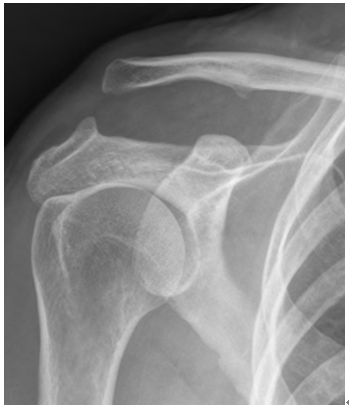

X-ray: AC 관절의 탈구 정도와 쇄골의 위치를 확인합니다. X-ray는 쇄골과 견봉 사이의 거리 증가를 보여줄 수 있습니다.